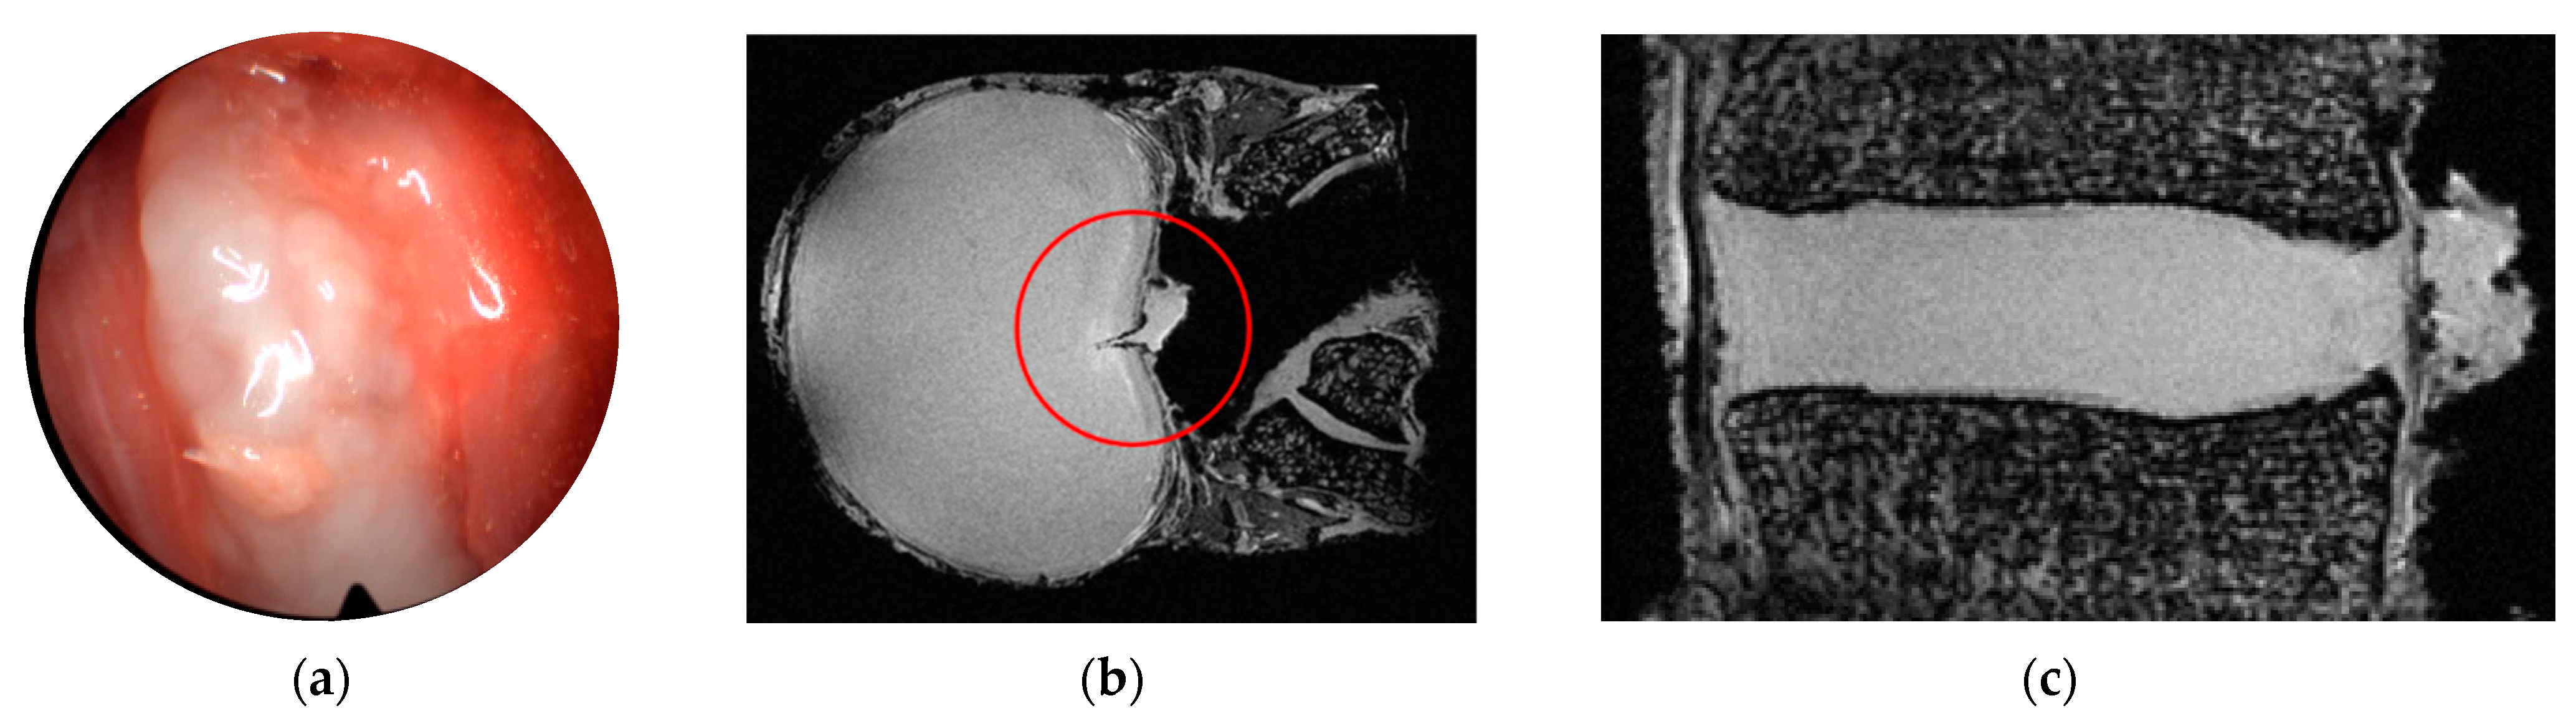

3.1. Provocation of Disc Herniation

3.2. Ultra-High Field MR Imaging